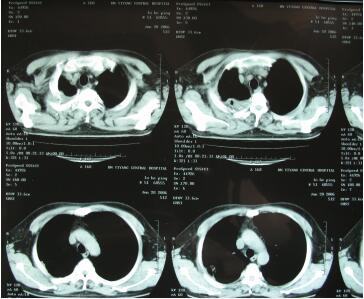

△手术中

元宵节一过,他便去当地医院复查,令他与医生吃惊的是,肿瘤缩小到2.6×1.3cm,这个结果一度让医生怀疑是仪器出现问题。而在三个月后的复查显示,肿瘤消失了!

△手术后CT显示